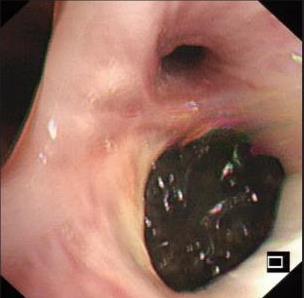

• 侵袭性肺真菌病的支气管镜表现及介入治疗效果

2025, 31(9):81-90. DOI: 10.12235/E20250317

摘要 (112) HTML (56) PDF 6.06 M (77) 评论 (0) 收藏

摘要:目的 探讨侵袭性肺真菌病(IPFD)的支气管镜表现,并评估介入治疗的安全性和疗效。方法 回顾性分析2018年5月12日-2025年5月12日于该院行支气管镜检查的35例IPFD患者的临床资料,观察IPFD的支气管镜表现及介入治疗效果。结果 共收集35例患者临床资料。其中,男22例,女13例,患者年龄(53±14)岁。基础疾病包括:血液系统恶性肿瘤10例,长期应用糖皮质激素者5例,2型糖尿病者4例,肺部恶性肿瘤2例,器官移植1例。胸部CT显示:肺部病变累及单肺叶者19例,累及多肺叶者16例。支气管镜下表现主要为:黏膜充血水肿29例(82.9%)、坏死物堵塞管腔22例(62.9%)、大量黏稠脓性分泌物17例(48.6%)、支气管部分狭窄或闭塞16例(45.7%)、黏膜坏死9例(25.7%)、黏膜出血5例(14.3%)、真菌球3例(8.6%)。其中,32例(91.4%)接受全身性抗真菌治疗,17例(48.6%)接受支气管镜局部两性霉素B灌注治疗,10例(28.6%)采用活检钳钳除病灶,6例(17.1%)采用冷冻探头冻取病灶,4例(11.4%)接受氩气刀治疗。28例(80.0%)临床症状明显改善,肺部影像学病灶缩小或消退;4例(11.4%)病灶稳定;3例(8.6%)未完成治疗。结论 IPFD多见于免疫抑制宿主,支气管镜常表现为:坏死物堵塞管腔、伴脓性分泌物、支气管管腔狭窄和局部黏膜充血水肿或坏死。全身抗真菌药物联合支气管镜下介入治疗,安全性高,且疗效好。